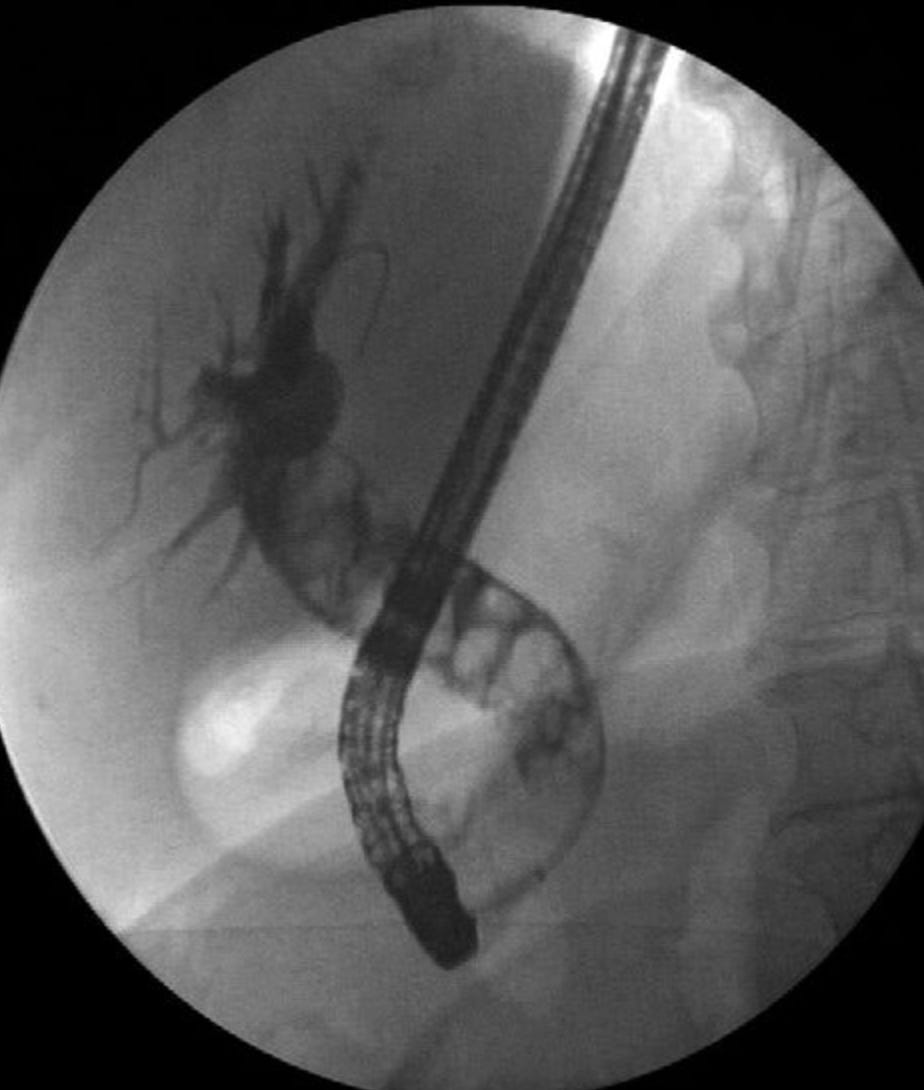

That’s an XR of a swollen bile duct absolutely packed with gallstones. Like a packet of smarties!

Common bile duct stones present unique challenges. These can form primarily in the ducts or migrate from the gallbladder. When stones obstruct bile flow, patients develop jaundice, dark urine, and pale stools. Add infection, and you have ascending cholangitis – a medical emergency requiring urgent intervention.

ERCP (Endoscopic Retrograde Cholangiopancreatography) is used for bile duct stone management. This procedure combines endoscopy with fluoroscopy to visualise and clear bile ducts. The procedure carries significant risk, making patient selection crucial. Read here for more! ERCP Guide